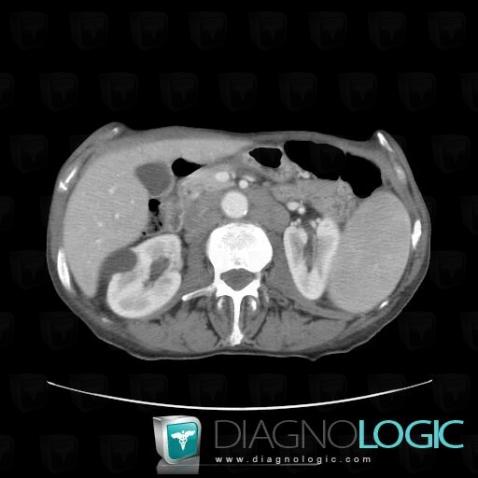

Lymphoma, Small bowel, CT

Here is the specific information in the key image above:

- Diagnosis Lymphoma, Location(s) Small bowel, with gamuts Terminal ileum lesion, Small bowel mass or filling defect, Focal thicknening of small bowel wall